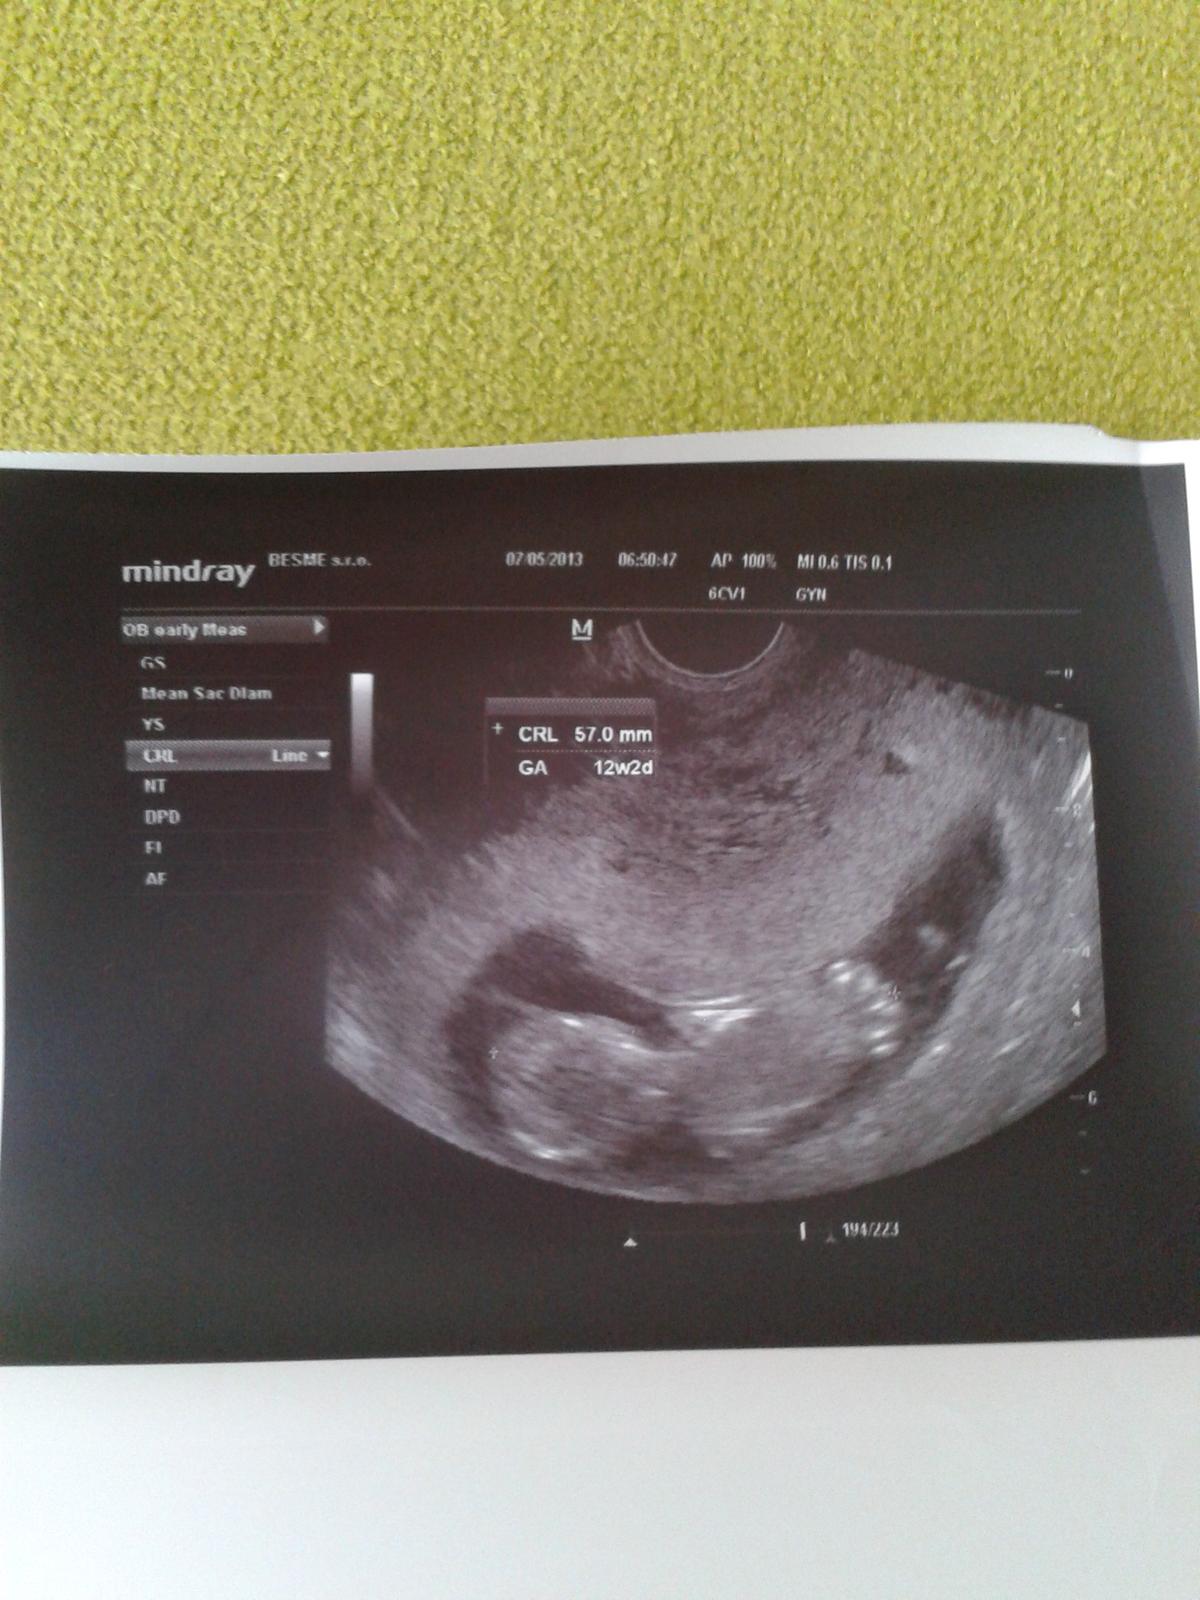

Ahojte babenky,tak uz som v 12 t a chcem vam ukazat moju prvu fotecku....moooc sa tesim a chcem sa s vami o to podelit 😉 😵

@slniecko2551 už je bábätko krásne vidieť, blahoželám 🙂

@slniecko2551 supeeeeer, gratulujem. Len tak dalej, nech pekne rastie 😉

@slniecko2551 jeeeej moja,to je prekrasna foto!drzkajte sa!